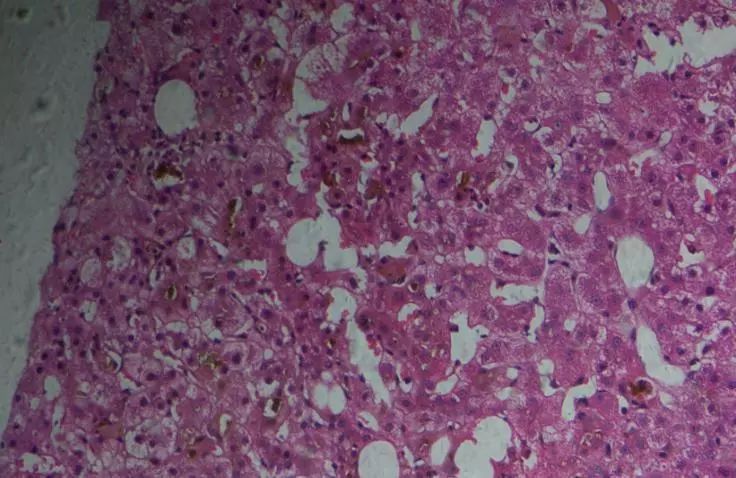

图3 患者的病理切片(HE染色)

患者肝脏病理解读(图3、4):肝细胞少许灶性坏死和炎症,轻度界面炎,毛细胆管、肝细胞、胆小管均有淤胆,波及3、2、1区,汇管区无水肿、散在中性多核细胞浸润,未见大量单核细胞,CD38阳性细胞相对较多。未见胆小管的明显异常。汇管区无明显纤维化,中央静脉及窦周纤维化。

病理诊断:急性炎症,胆汁淤积症,非酒精性脂肪性肝炎(NASH)。